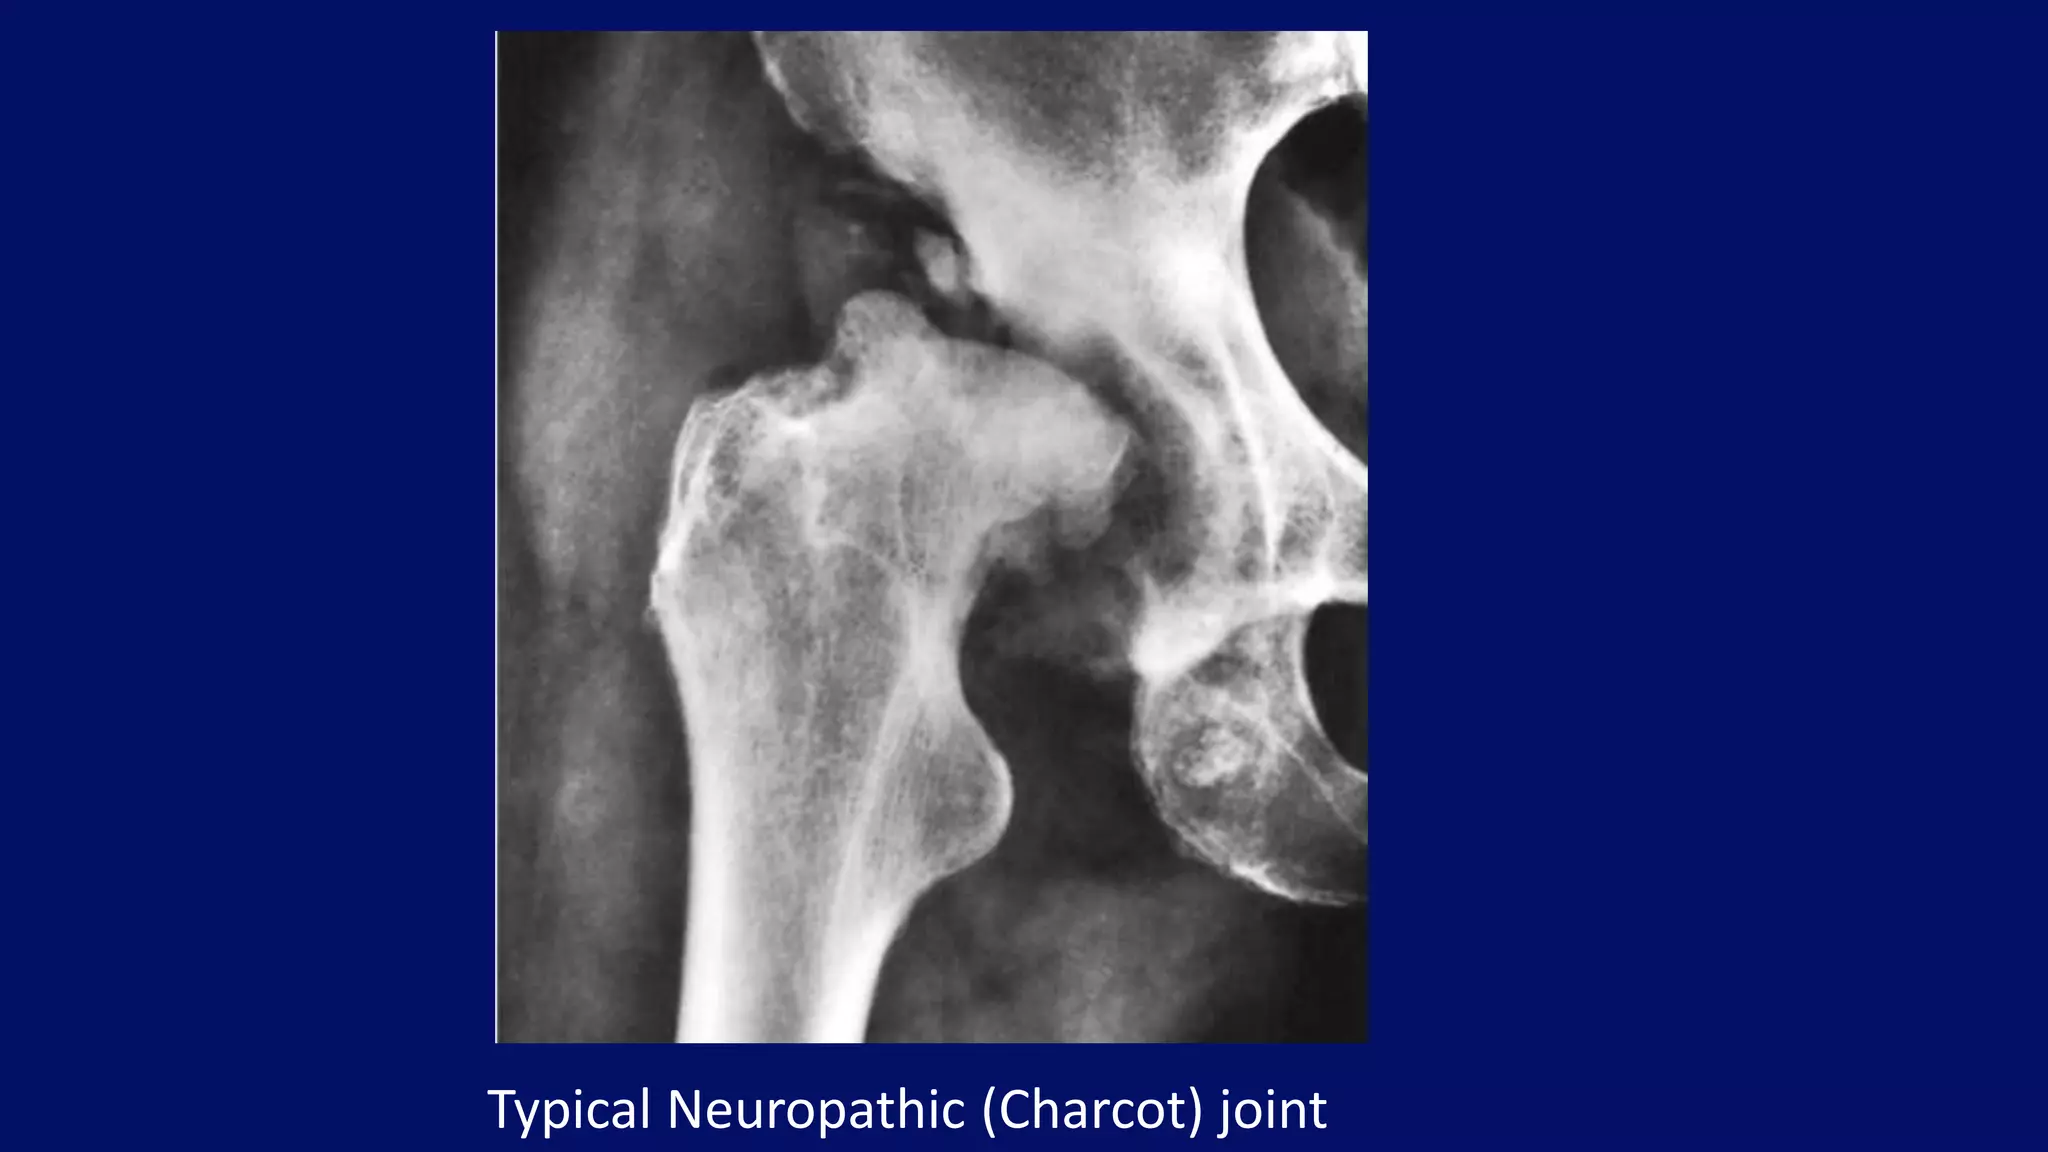

Typical Neuropathic (Charcot) joint

• #50 Neuropathic joint. Anteroposterior radiograph of the right hip of a 57-year-old woman with neurosyphilis (tabes dorsalis) shows the typical features of neuropathic (Charcot) joint. There is complete disorganization of the joint, fragmentation, and subluxation. The absence of osteoporosis is a characteristic feature of the neuropathic joint. This condition represents the most severe manifestation of degenerative joint disease.